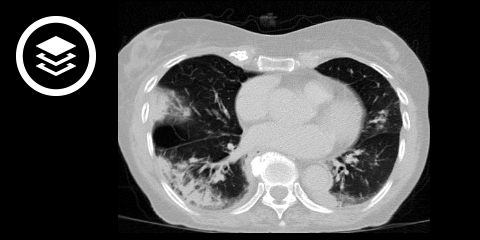

Bei Pneumonien unterscheidet man zwischen folgenden Verschattungstypen:

Alveoläre Verschattungen sind i.d.R. im Röntgen-Thorax zu erkennen. Interstitielle Verschattungen sind hingegen oft nur unzureichend erkennbar. Bei unklaren Befunden und Verdacht auf eine atypische bzw. interstitielle Pneumonie sollte daher eine CT- bzw. HR-CT-Untersuchung durchgeführt werden.

Ein alveoläres Verschattungsmuster ist typisch für eine alveoläre Pneumonie. Ein segmentaler oder lobärer Befall stellt sich meist in Form einer homogenen alveolären Verschattung (Konsolidierung) dar. Häufig ist ein positives Bronchopneumogramm erkennbar. Eine Wölbung der Lungenfissuren aufgrund von massivem Exsudat ist typisch für eine Pneumonie mit Klebsiella pneumoniae.

Bei multiplen kleineren, unscharf begrenzten, konfluierenden und somit nicht anatomisch begrenzten Verschattungen spricht man von bronchopneumonischen alveolären Verschattungen. Diese sind häufig multifokal und bilateral in den dorsalen Unterlappenabschnitten (Segmente 6 und 10) lokalisiert. Bei schwerem Verlauf kann die Bronchopneumonie auch den ganzen Lungenlappen betreffen. Die Randbegrenzungen sind unregelmäßig; Segment- und Lappengrenzen werden nicht respektiert. Volumenvermehrende Infiltrate, dystelektatische Areale und fokale Überblähungen führen dazu, dass Bronchopneumonien insgesamt volumenneutral oder bei Überwiegen der Atelektasen sogar volumengemindert erscheinen. Weitere Befunde sind Verdickungen und unscharfe Begrenzungen der Bronchialwand und der begleitenden Lungenarterie.

Befundbeispiele

- Bildquelle DICOM-Viewer (Covid-19 Pneumonie): Deai et al. (2020). Data from Chest Imaging with Clinical and Genomic Correlates Representing a Rural COVID-19 Positive Population [COVID-19-AR-16434453. The Cancer Imaging Archive

- Bildquelle DICOM-Viewer (Pneumonie): Datensatz freundlicherweise zur Verfügung gestellt durch die Klinik für diagnostische und interventionelle Radiologie, St. Vinzenz Hospital Köln